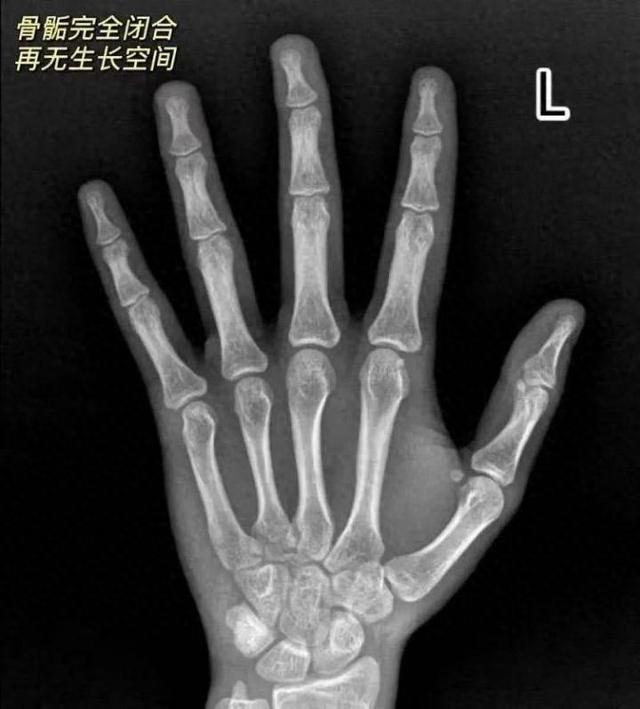

经检查发现,凯凯骨龄已达18岁、骨骺闭合,成年身高定格157厘米,而其遗传身高本可达到170±5厘米。